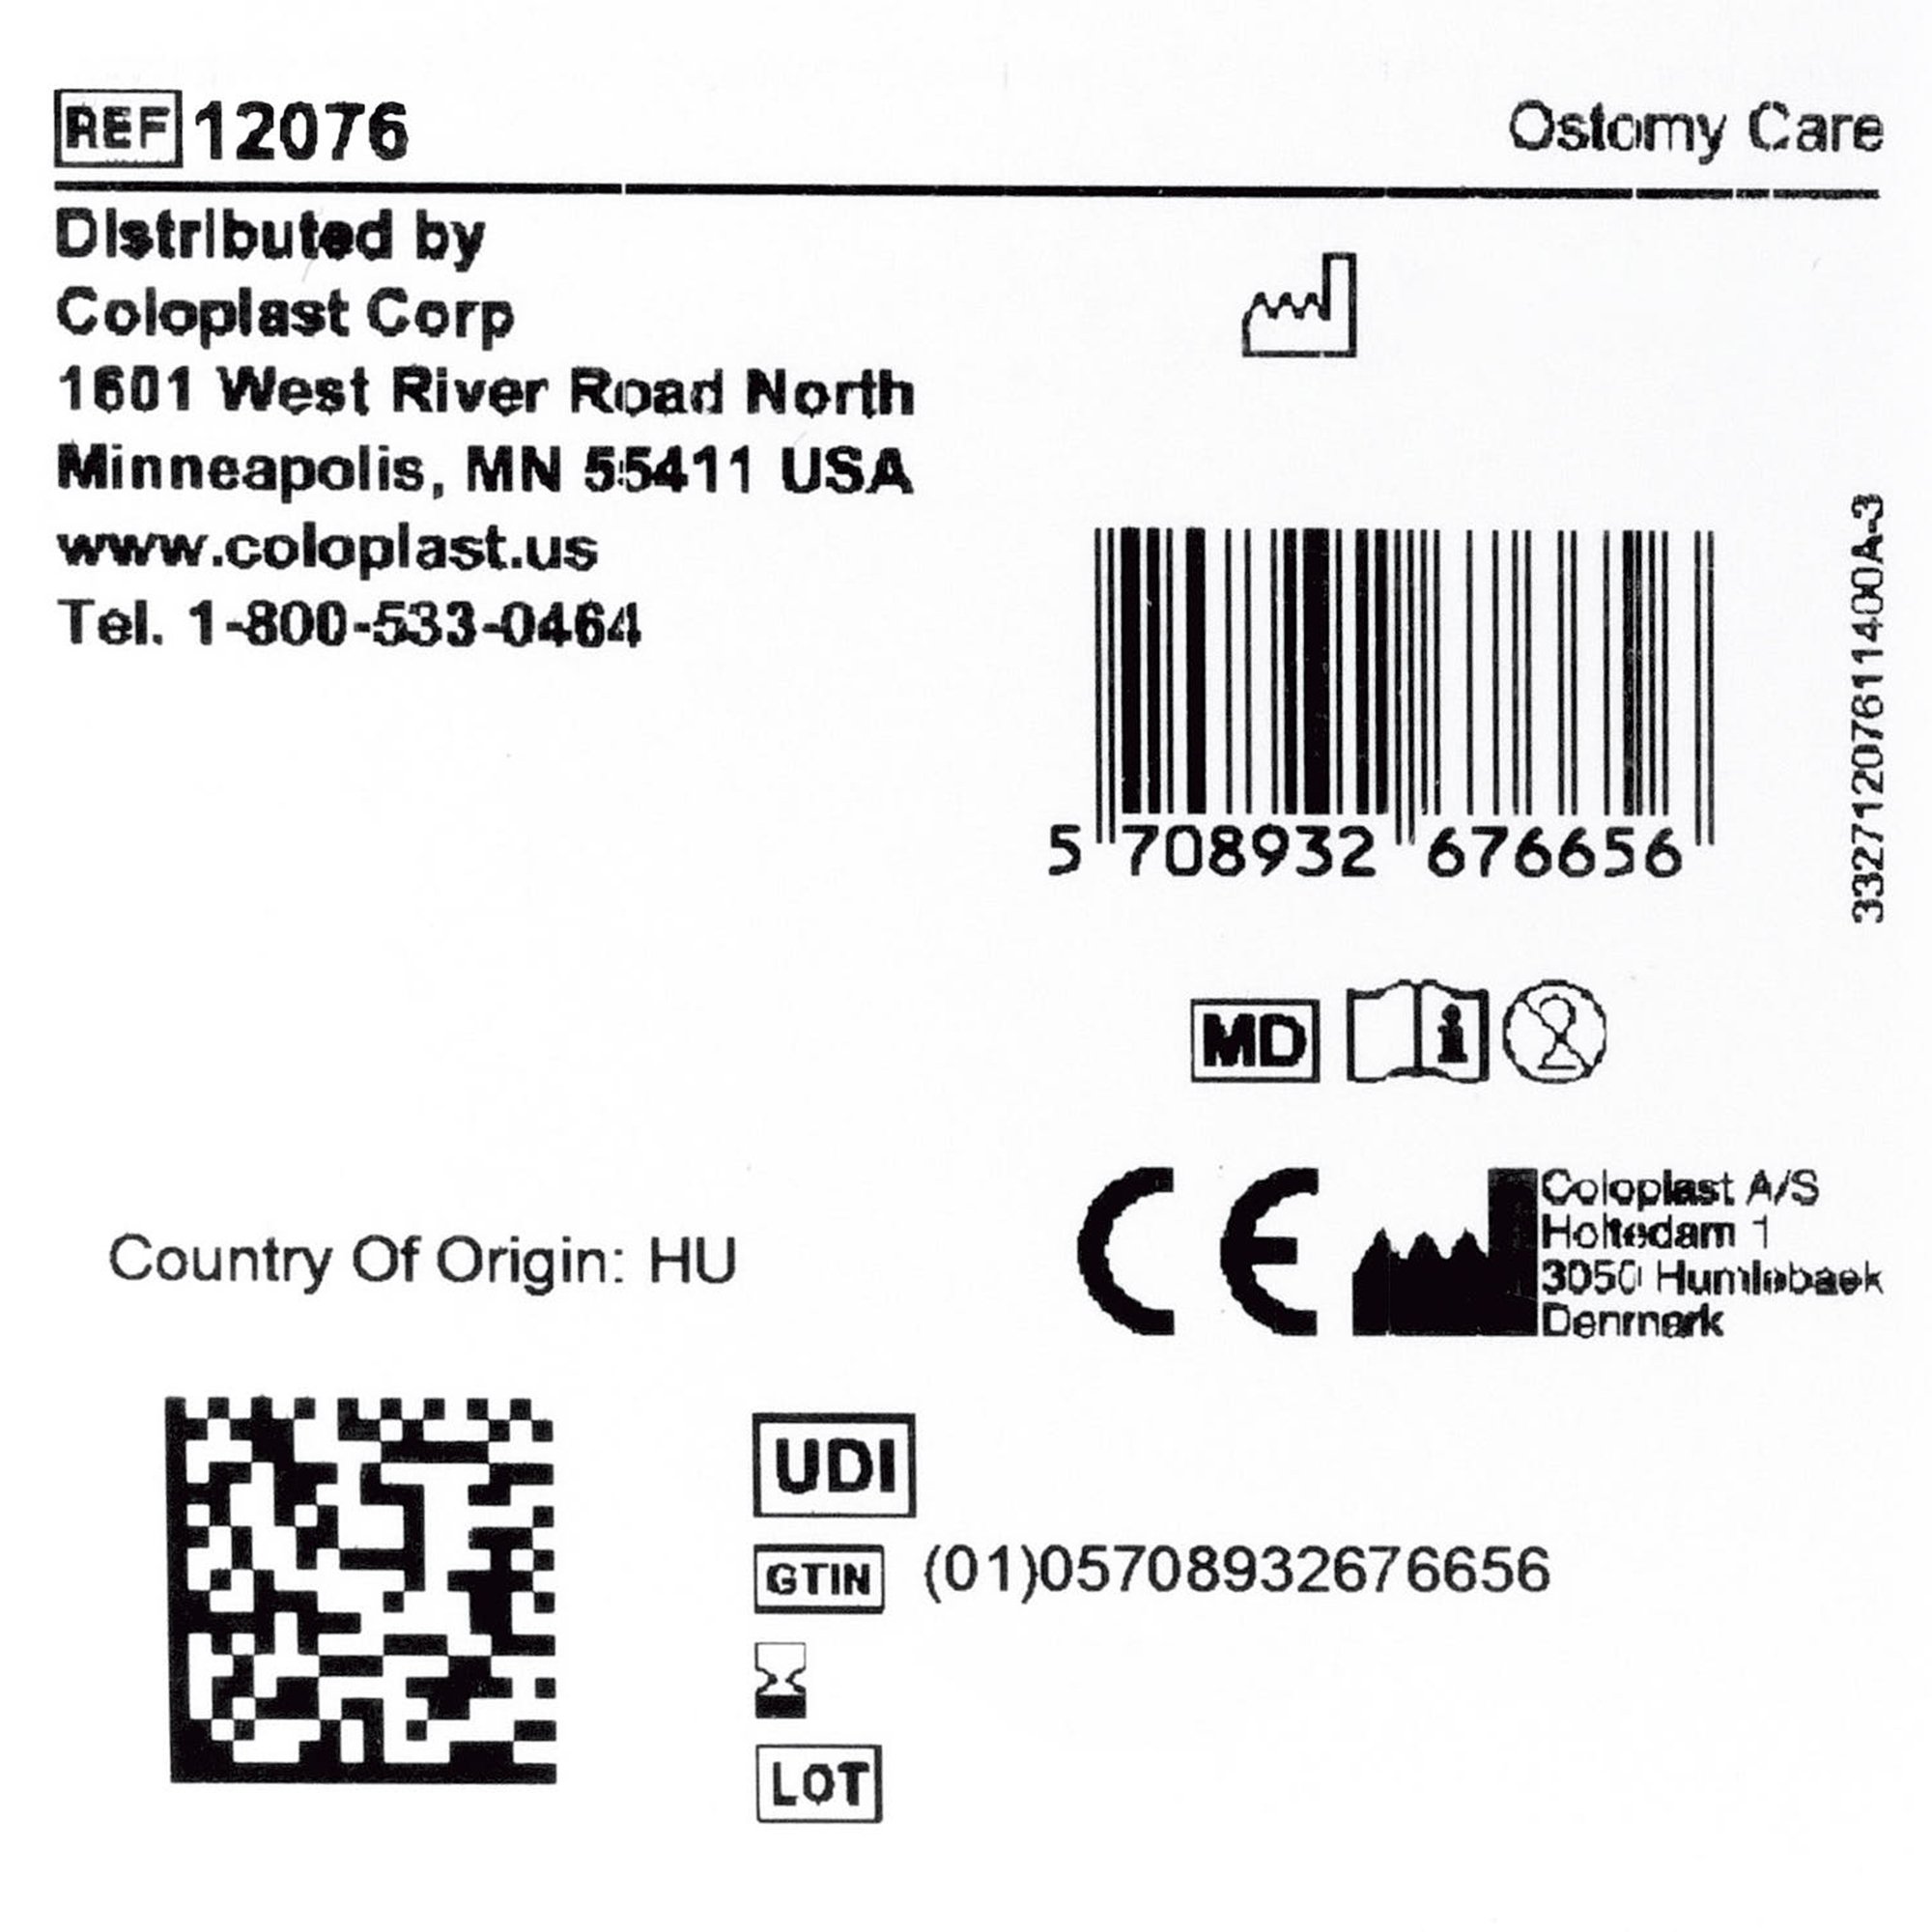

Brava® Thick Skin Barrier Ring 1-3/8 Inches for Ostomy Protection